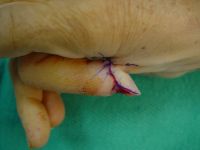

| Case

3. This gentleman sustained partial amputations of all fingers in an industrial press. His index finger was the only digit with a potentially salvageable fingertip. |

| Distal phalanx

fracture stabilization. Pins were placed to protrude

proximally in anticipation of flap cover. |